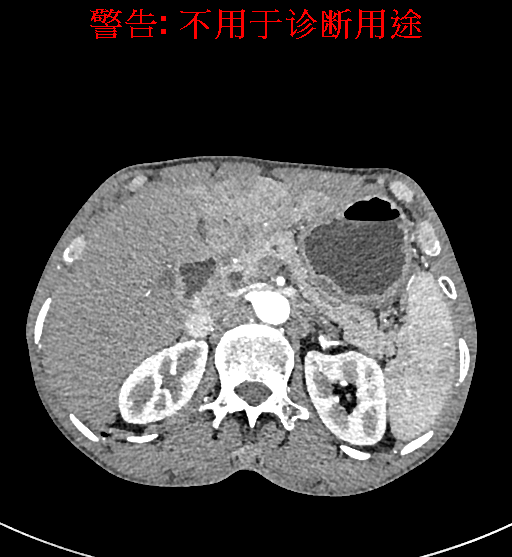

实验室检查: 血常规:WBC 4.89*109/L,RBC 3.64*1012/L, HB 119.00g/L, HCT 35.40%,PLT 123*109/L,RET% 0.48%, RET 0.017*1012/L, IRF 2.00%生化全套:ALT 56.00U/L AST 60.00U/L, LDH 312.00U/L TP 72.08g/L ALB 32.44g/L, GGT 101.00U/L,TBA 21.90umol/L,A/G 0.82,ADA 23.00U/L, PAB 94.20mg/L, CHE 5405.00U/L 肿瘤标志物:CEA 2.80ng/mL CA19-9 11.46U/ml 肝炎全套: HAV-IgM 0.21S/CO, HBcIgM 0.330S/CO, HCV-cAg 0.08S/CO, HEV-IgM 0.03S/CO, HBeAg 6.000S/CO 诊疗过程: CT结果输入海信CAS系统后行3D重建及手术规划后,于2018-5-17局麻下行“经皮肝动脉造影术+肝动脉化疗栓塞术”手术治疗 术前三维重建及手术方案设计: 将0.625mm双源薄层CT资料的静脉期和动脉期Dicom格式文件导入海信CAS系统。 通过调节窗宽窗位调整CT序号,对肿瘤,肝实质,胆囊,下腔静脉,肿瘤,肝动脉、门静脉及肝静脉等进行三维重建;系统自动计算肿瘤体积和肝脏体积。肝脏体积为1563ml,肿瘤体积为537.6ml,通过比对50-60岁正常肝脏体积为1343.28±246.69ml。 手术步骤: 常规准备后,患者仰卧于DSA手术床。常规双侧股动脉区域消毒,铺巾。2%利多卡因局部麻醉右侧股动脉区成功后,应用Seldinger技术穿刺右侧股动脉,置入5F动脉鞘。送5F 肝导管至腹腔干、肝动脉造影,肝区可见团块状及多发结节状肿瘤染色、侵犯门静脉左支。静脉推注维瑞特5mg后,透视下将微导管分别超选择至各支肿瘤供血动脉内,应用雷替曲塞4mg+奥沙利铂50mg+表柔比星20mg +LP 10ml的混合液及适量350-560um明胶海绵进行栓塞,后造影示栓塞适量,退出导管、血管鞘,局部压迫10min,加压包扎。患者术中未诉不适,术后平车安返病房。随访情况: 患者术后3月复查上腹CT示肝左叶病变活性残留,腹腔内、腹膜后多发略大淋巴结,部分较前略减小,今患者为求进一步诊治,与我院再次行“肝动脉造影+经导管肝动脉栓塞术”,术后2周无明显不适 术前CT检查:动脉期

静脉期